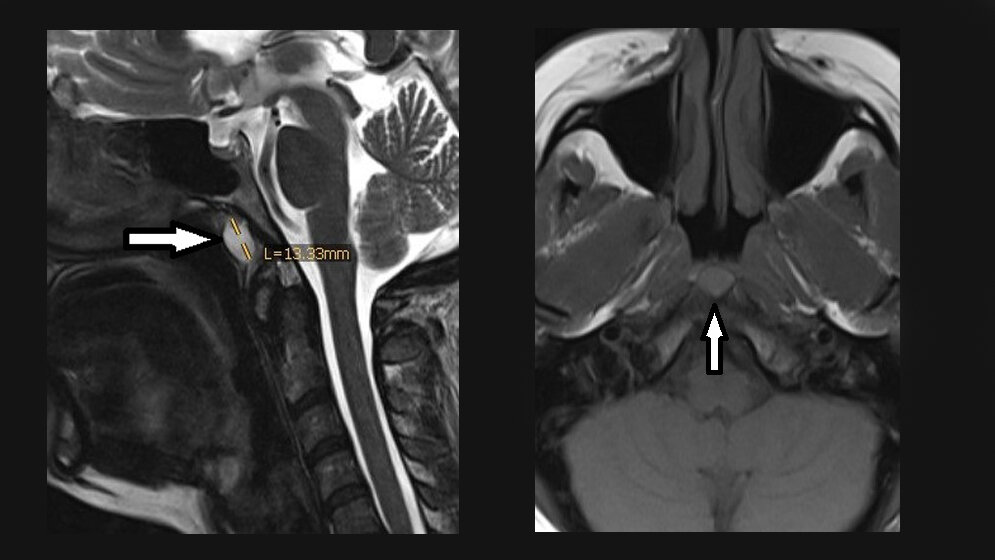

Die Tornwaldt-Zysten treten in der Mittellinie des Nasopharynx oberhalb des oberen Schlundschnürers auf. Die Zyste kann mit Einschränkung der Nasenatmung, laufender Nase, Hörstörung und anderer unspezifischer klinischer Manifestation vergesellschaftet sein. Obwohl selten vorkommend, sollte sie auch in die Differenzialdiagnose von Nackenschmerzen und Bewegungseinschränkung einbezogen werden.

Tornwaldt cysts occur in the midline bursa of the nasopharynx above the upper border of the superior constrictor muscle. Sometimes the cyst is associated with the obstruction of nasal breathing, runny nose, hearing impairment, and other non-specific clinical manifestations. Although rare, it should be kept as a differential diagnosis for cervical myalgia and stiffnes.